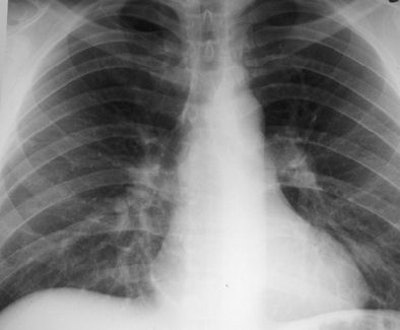

These are your lungs on crack

On x-rays, acute lung injury after cocaine use can appear as "bilateral, perihilar areas of increased opacity or attenuation, usually without pleural effusion or cardiomegaly," according to Dr. Michael Gotway and colleagues from San Francisco General Hospital; the University of California, San Francisco; and Brigham and Women's Hospital in Boston. "High-resolution CT may show multifocal ground-glass attenuation associated with septal thickening," but the condition clears up quickly after discontinuing cocaine use, they reported (RadioGraphics, October 2002, Vol. 22:4, pp. S119-S135).

| Acute lung injury (crack lung) in a 37-year-old man who presented with shortness of breath and cough after crack use. Above, frontal chest radiograph reveals ground-glass areas of increased opacity in the right lower lobe (arrow), a finding that is consistent with numerous causes, including edema, infection, hemorrhage, and aspiration. Below, high-resolution CT scan (level = -700 HU, window width = 1,000 HU) reveals ground-glass attenuation (arrows) with interlobular septal thickening (arrowheads). The differential diagnosis of these findings includes infection (especially Pneumocystis carinii pneumonia), lipoid pneumonia, and alveolar proteinosis, among numerous other causes. Bottom, frontal chest radiograph obtained two days after CT shows resolution of the increased opacity. Fig. 3a, b, c. Gotway MB, Marder SR, Hanks DK, et al. "Thoracic Complications of Illicit Drug Use: An Organ System Approach." RadioGraphics. 2002;222:S119-S135. |